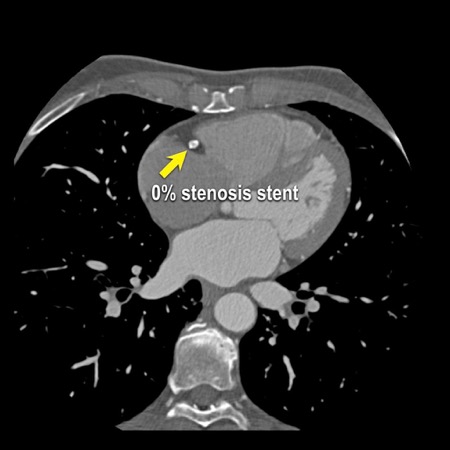

Modifier S – stent

The presence of a stent is indicated by modifier “S”.

Examples

- If a patient has a stent, showing no in-stent restenosis and a mild

(25-49%) stenosis in the coronaries, this patient classifies as CAD-RADS

2/S. - Similarly, a patient with no in-stent restenosis but severe (70-99%)

stenosis in a coronary other than LM classifies as CAD-RADS 4A/S. - If there is a severe (70-99%) in-stent restenosis in a coronary other

than LM, this patient classifies as CAD-RADS 4A/S. - If the stent is non-diagnostic and there is no >49% stenosis present

in the coronaries, the patient classifies as CAD-RADS N/S.

Note: the location of the stenosis does not matter, when using

CAD-RADS.

What matters is that the patient has a severe stenosis and needs further

management.

Please note: total coronary plaque burden should also be added and is

placed before the modifier S.